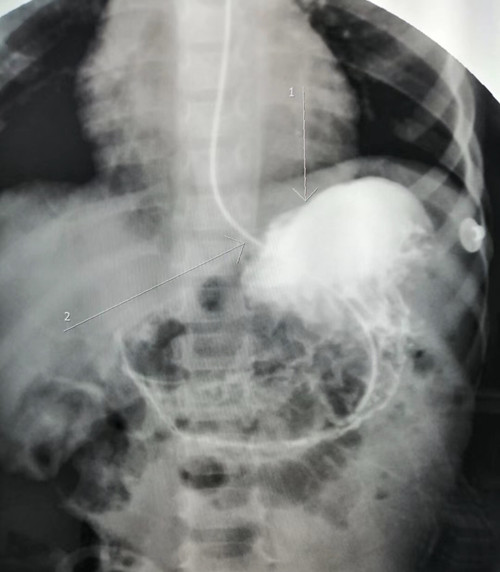

4月,儿外科联合儿内科、麻醉科成功救治一名急性胃扭转患儿。患儿3岁,因“呕吐一天,发热半天”入住我院东区医院儿科病房,胃肠减压出上千毫升液体,检查合并胰腺炎,经儿内科紧急抢救,急查腹部CT、上消化道造影提示胃扭转。儿外科团队和麻醉科评估合作,为患者实施腹腔镜下手术,术中发现患儿胃体180°扭转,脾脏向后移位,导致胰尾部扭转。医护团队团结协作,成功为患儿实施了腹腔镜下胃扭转复位手术,将脾脏和胃固定于正常位置。术后,在儿内外科医护团队悉心照料下,患儿顺利康复出院。据了解,小儿慢性胃扭转比较常见,但如此危重的急性胃扭转十分罕见,此手术也是扬州地区首例在腹腔镜下实施的低龄危重患儿的胃扭转手术。通过与儿内科副主任陈晓带领的医护团队的通力协作,今年疫情期间,儿外科已成功救治了多例肠扭转后合并胃肠功能瘫痪和腹膜炎合并休克的危重患儿。